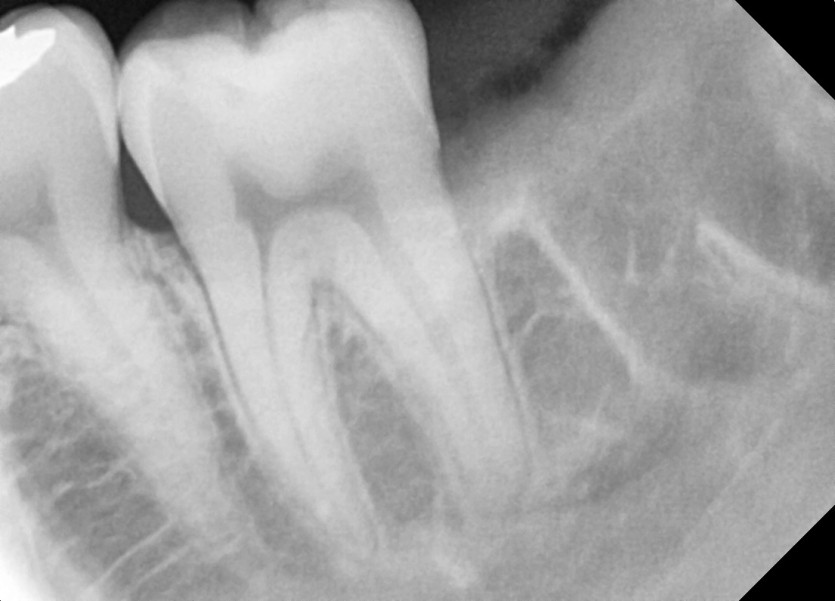

#28,38 사랑니 발치

구강 외과 전문의가 당일 발치했습니다.